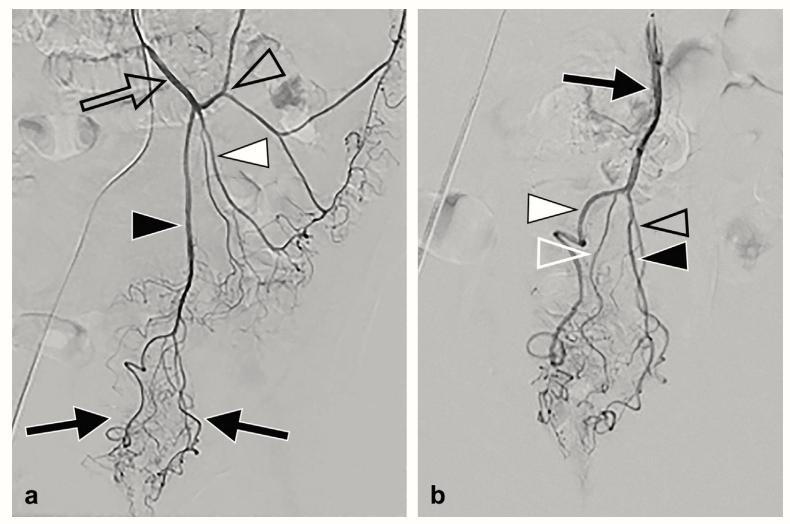

图2.数字减影肠系膜下动脉造影术。

- 肠系膜下动脉选择性血管造影(开放箭头)显示直肠上动脉(黑色箭头)及其左右分支(黑色箭头),乙状结肠动脉(白色箭头),左结肠动脉(开放箭头)。

- 直肠上动脉的亚选择性血管造影(黑色箭头)显示分支进入右前(白色箭头)、右后(开放的白色箭头)、左前(黑色箭头)和左后(开放的黑色箭头)分支。